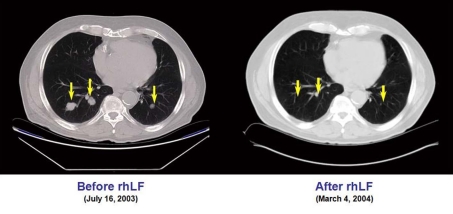

This patient underwent nephrectomy in 2002 for renal cell carcinoma. Lung metastases were diagnosed 6 weeks post-operatively and the patient was treated with capecitabine, interferon-α, gemcitabine, and thalidomide. After initial improvement, he progressed and entered the talactoferrin trial in August 2003. He had a partial response and then remained stable by RECIST criteria until July 2006. His tumor regression during the first 17 months of therapy is summarized graphically in Figure 1. Serial CT scans, seen in Figure 2, show the reduction in size of his pulmonary metastases. The patients cancer later progressed in the mediastinum and brain, and he expired in September, 2006.

Figure 2.

CT scans showing the reduction in size of the pulmonary metastases in case 4.